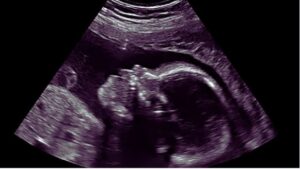

अब नेपाल, श्रीलंका और थाईलैंड में भ्रूण लिंग जांच के लिए Active Gang. STF ने 9 जिलों पर रखी नजर. गर्भपात के 125 मामले दर्ज.

Chandigarh : हरियाणा में सरकार की सख्ती के चलते लिंग जांच गिरोह अब पड़ोसी राज्यों के बजाय विदेशों में सक्रिय हो गया है… बेटे की चाहत में दंपती Nepal, Srilanka, Thailand जैसे देशों में भ्रूण लिंग जांच करा रहे हैं. इसका कारण यह है कि स्वास्थ्य विभाग पड़ोसी राज्यों पंजाब, उत्तर प्रदेश, राजस्थान और दिल्ली में लिंग जांच सेंटरों के खिलाफ लगातार कार्रवाई कर रहा है.

स्वास्थ्य विभाग के अनुसार भ्रूण लिंग जांच गर्भधारण के 13 से 18 सप्ताह के बीच होती है, जबकि गर्भपात आमतौर पर 20 सप्ताह तक किया जाता है. मेडिकल टर्मिनेशन ऑफ प्रेगनेंसी (MTP) संशोधन कानून 2021 के तहत 12 से 20 सप्ताह तक गर्भपात के लिए एक स्त्री रोग विशेषज्ञ और 20 से 24 सप्ताह तक के लिए दो महिला डॉक्टरों की सलाह जरूरी है. गर्भपात के लिए लिखित कारण देना अनिवार्य है, जिसके चलते अवैध गर्भपात रोकना स्वास्थ्य विभाग के लिए चुनौती बना हुआ है.